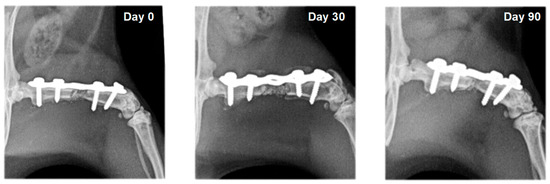

3.2. Radiography